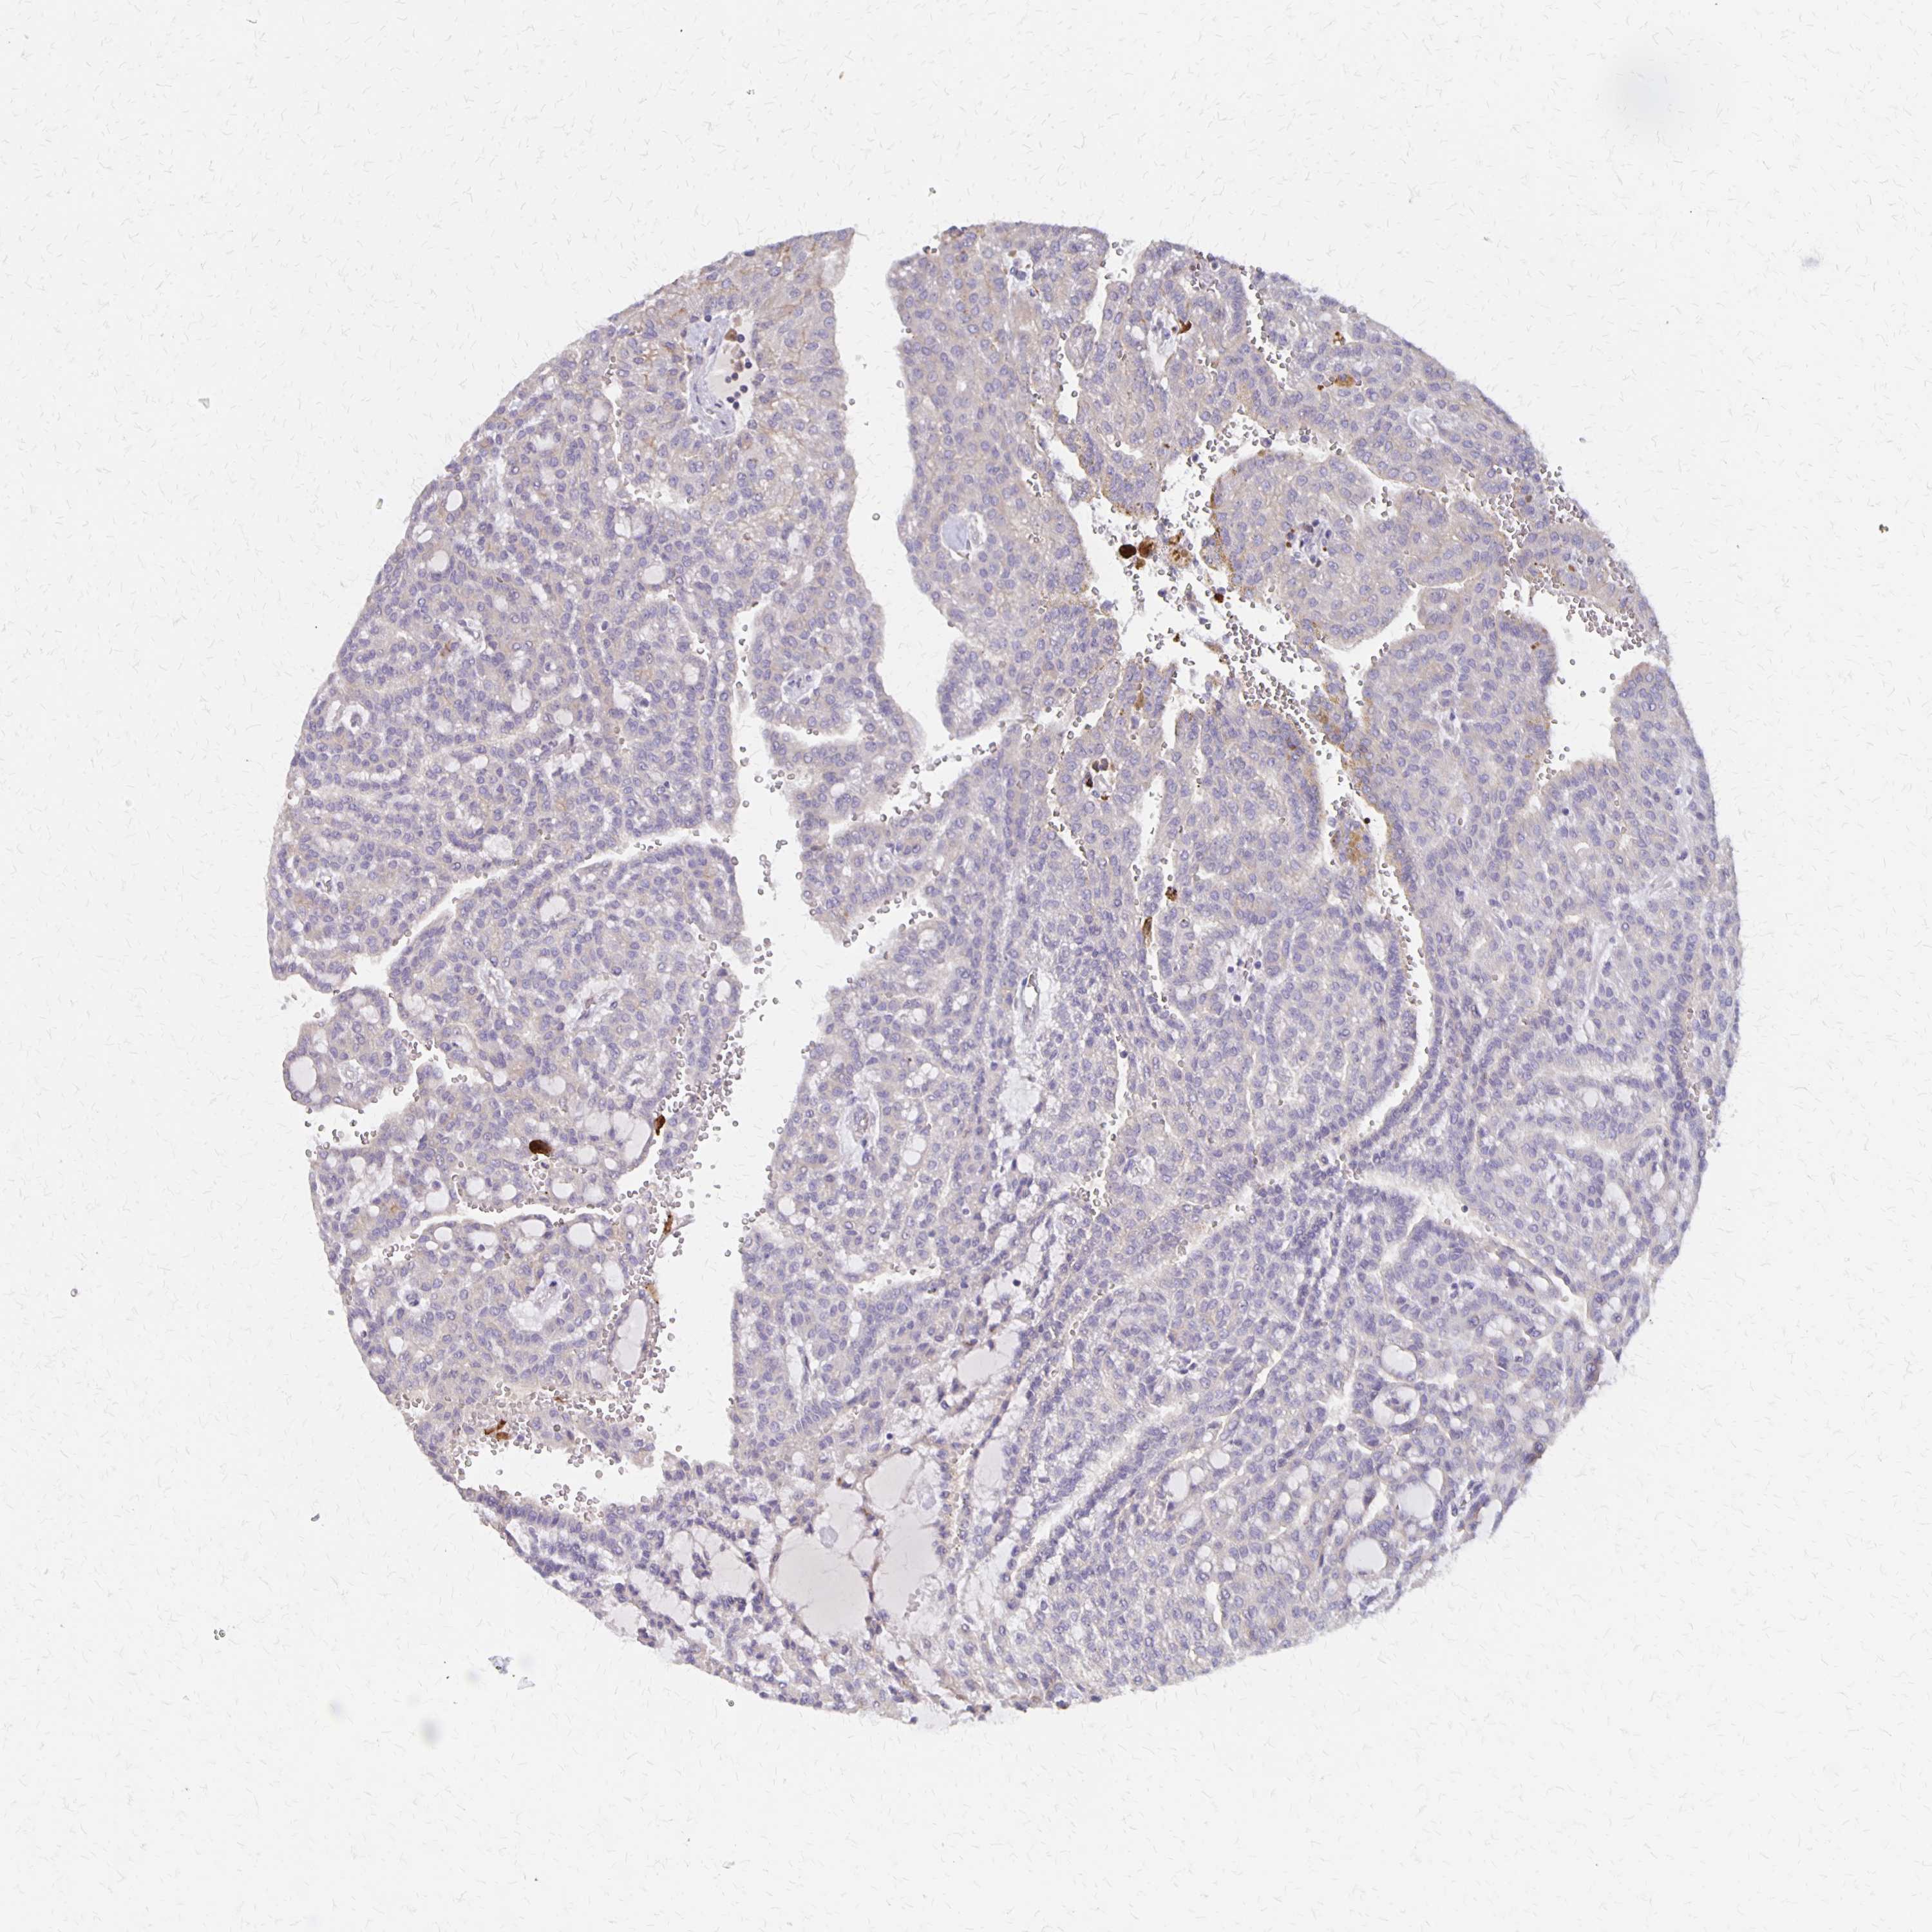

KIDNEY RENAL CLEAR CELL CARCINOMA (VALIDATION) - Interactive survival scatter ploti

The Survival Scatter plot shows the clinical status (i.e. dead or alive) for all individuals in the patient cohort, based on the same data that underlies the corresponding Kaplan-Meier plots. Patients that are alive at last time for follow-up are shown in blue and patients who have died during the study are shown in red.

The x-axis shows the expression levels (FPKM) of the investigated gene in the tumor tissue at the time of diagnosis. The y-axis shows the follow-up time after diagnosis (years). Both axes are complimented with kernel density curves demonstrating the data density over the axes. The top density plot shows the expression levels (FPKM) distribution among dead (red) and alive patients (blue). The right density plot shows the data density of the survived years of dead patients with high and low expression levels respectively, stratified using the cutoff indicated by the vertical dashed line through the Survival Scatter plot. This cutoff is automatically defined based on the FPKM cutoff that minimizes the p-score. The cutoff can be changed by dragging the vertical line or by entering a cutoff value in the square labeled "Current cut-off".

Under the Survival Scatter plot the p-score landscape (black curve; left axis) is shown together with dead median separation (red curve; right axis). Dead median separation is the difference in median mRNA expression between patients who have died with high and low expression, respectively. It is calculated as follows: median FPKM expression of dead patients with high expression - median FPKM expression of dead patients with low expression. This is intended to aid the user in visually exploring custom cutoffs and the associated p-scores and dead median separation.

Individual patient data is displayed and can be filtered by clicking on one or more of the category buttons on the top of the page. Categories describing expression level and patient information include: high, low, alive, dead, female, male and tumor stages. The scale of the x-axis can be toggled between linear and log-scale by clicking on the "x log" button. Mouse-over function shows TCGA ID, patient information and mRNA expression (FPKM) for each patient.

& Survival analysisi

Kaplan-Meier plots summarize results from analysis of correlation between mRNA expression level and patient survival. Patients were divided based on level of expression into one of the two groups "low" (under cut off) or "high" (over cut off). X-axis shows time for survival (years) and y-axis shows the probability of survival, where 1.0 corresponds to 100 percent.

NOG is not prognostic in Kidney Renal Clear Cell Carcinoma (validation)

Best expression cut offi

Based on the FPKM value of each gene, patients were classified into two groups and association between prognosis (survival) and gene expression (FPKM) was examined. The best expression cut-off refers the FPKM value that yields maximal difference with regard to survival between the two groups at the lowest log-rank P-value. Best expression cut-off was selected based on survival analysis .

When clicking on this number, the vertical dashed line indicating cut-off, the interactive survival plot, and the Kaplan-Meier curve will be adjusted to show results based on the best expression cut-off.

: 2.53

P scorei

Log-rank P value for Kaplan-Meier plot showing results from analysis of correlation between mRNA expression level and patient survival.

N/A

Average pTPM 5.5

Number of samples 100